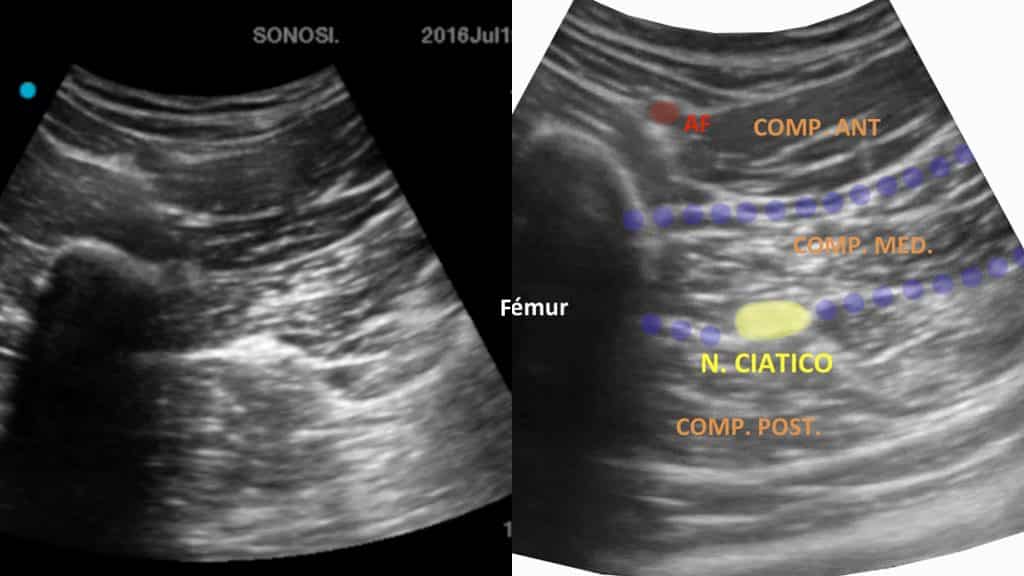

Localización ecográfica: colocaremos la sonda de ultrasonidos 8-10 centímetros por debajo del pliegue inguinal, identificando el compartimento anterior del muslo con los vasos femorales, en un nivel mas profundo encontraremos el compartimento medio con el músculo adductor mayor, y posteriormente el compartimento profundo con los músculos isquiotibiales. Entre el compartimento medio y posterior identificaremos el nervio ciático.

Paciente en posición de decúbito supino que permite realizar el bloqueo sin movilizar al paciente. El anestesiólogo se coloca en el lado contralateral al miembro a bloquear con el objetivo de realizar la punción en plano.

En la imagen ecográfica localizamos los vasos femorales en el compartimento anterior del muslo, el fémur y el nervio ciático entre el compartimento medio y el compartimento posterior.